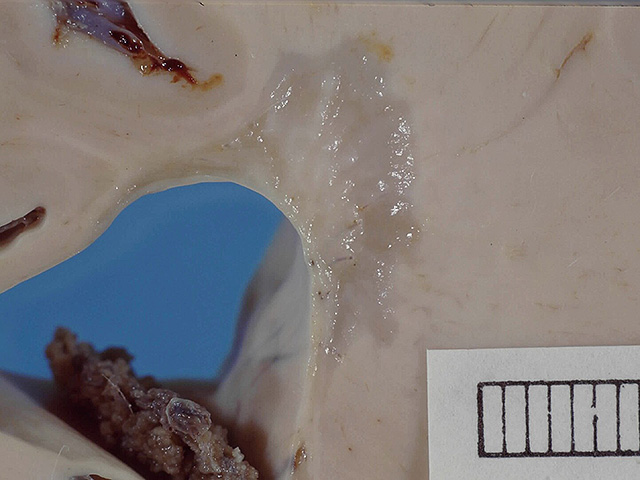

Wikipedia.org. Фото: Narraburra